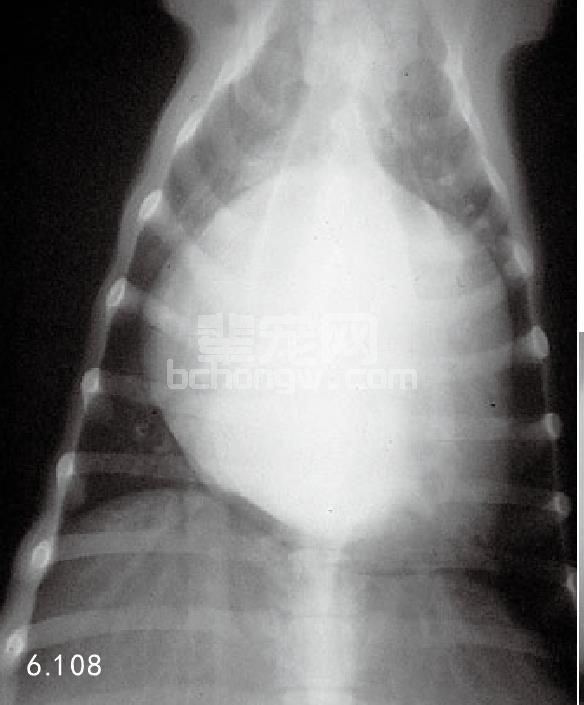

图6.108 背腹位胸部X线片(与6.107为同一患犬)。